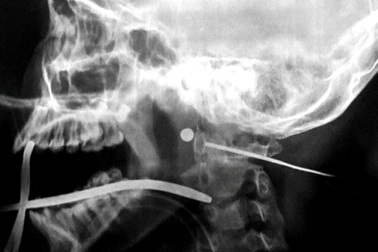

Ngồi chơi trước nhà, bé gái bị đạn bắn xuyên cổĐang ngồi chơi trong sân trước nhà, bé gái 12 tuổi bất ngờ đau đớn dữ dội ở cổ, máu trào ra ngoài. Tại bệnh viện, sau 4 giờ phẫu thuật khó khăn, bác sĩ đã gắp ra viên đạn bi đã gỉ sét, nghi là đạn của loại súng săn tự chế.